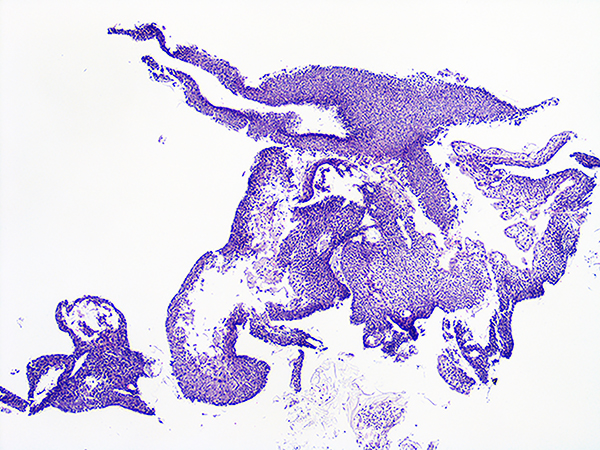

Case 3

Soft Bx CIN 2-3 10x - Low Power